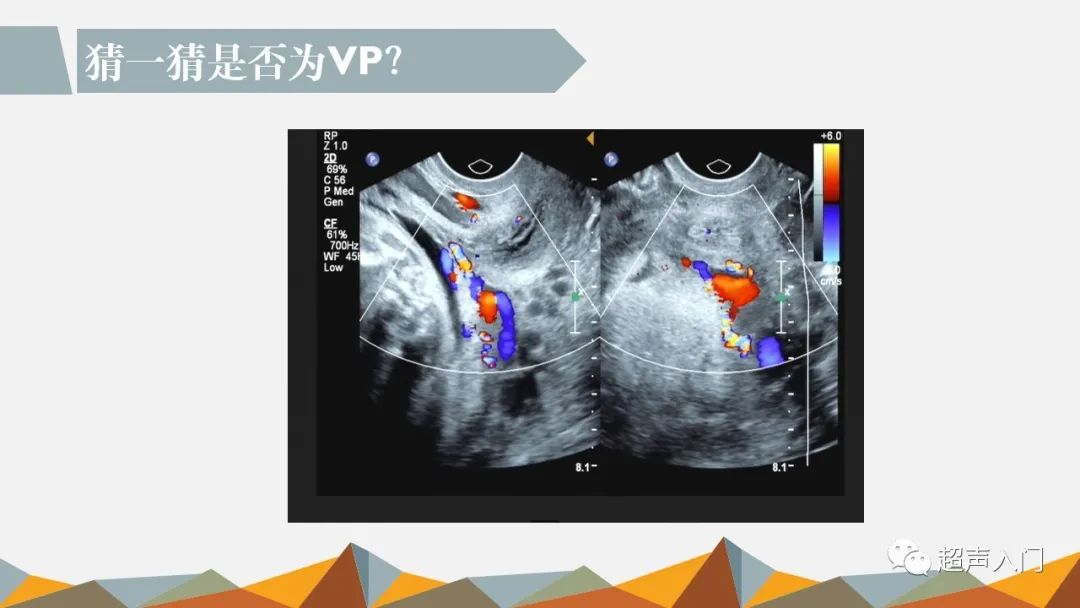

前置血管超声诊断思路

图片尺寸1080x608